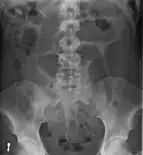

- Abdominal x-ray – tire-like shadow arising from right iliac fossa and passing to left

Coffee bean sign in a person with sigmoid volvulus

Plain X ray of a cecal volvulus